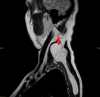

Figure 3. MRI Scan (Sagittal)

Figure 4